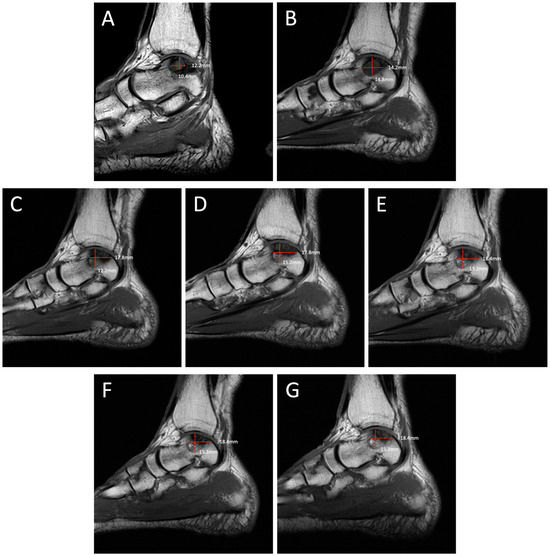

Degenerative progression of the left medial osteochondral lesion outlined in red on axial MRIs from 2009 to 2021. The timeline of lesion progression includes MRI scans from 2009 (

A), 2011 (

B), 2016 (

C), 2017 (

D), 2018 (

E), 2019 (

F), and 2021 (

G). This axial view demonstrates the osteoarthritic progression of the lesion from 12.2 mm × 11.2 mm in 2009 to 19.1 mm × 13.2 mm in 2021. Patient Case Report: A 72-year-old male presented to the outpatient foot and ankle clinic with a 16-year history of bilateral ankle pain. The patient’s symptoms first began in 2007 following an exercise-induced injury that was left untreated. The patient described his pain as an intermittent waxing and waning sensation of dull pain and aches. Physical examination demonstrated tenderness localized to the anterior aspect of both ankles. Ankle movements were free and without pain. Stability testing revealed mild increased laxity with anterior drawer and talar tilt. He had no other significant past medical history that would contribute to his orthopedic condition. Following his injury, the patient underwent bilateral ankle magnetic resonance imaging (MRI) beginning in 2009, which revealed osteochondral lesions of the talus (OLTs) in both ankles. The patient continued to receive serial ankle MRIs over the following years to monitor the course of the osteochondral lesions over time, totaling seven MRI scans between 2009 and 2021 (

Figure 1,

Figure 6). These serial images demonstrated large medial osteochondral lesions in each ankle that showed progressive growth in diameter over time. Though imaging has revealed the gradual growth of the lesions since their onset, the patient has remained relatively asymptomatic. The patient describes his symptoms as dull, intermittent pain that has not had a significant impact on his activities of daily living. However, the patient has had some modifications to his physical activities, including modifying his exercise from running to walking. Overall, the patient remains physically active and reports using an elliptical frequently with minimal pain. Given the patient’s functional abilities and relatively minimal symptoms, the decision was made to continue treatment through non-operative interventions, including monitoring the lesions through imaging and implementing rigid orthotics in his shoes for improved ankle stability. In the presented case, we illustrate the progression of bilateral OLTs over a 12-year time period. The left OLT in our patient progressed from 12.2 × 11.2 mm in 2009 to 19.1 × 13.2 mm in 2021.